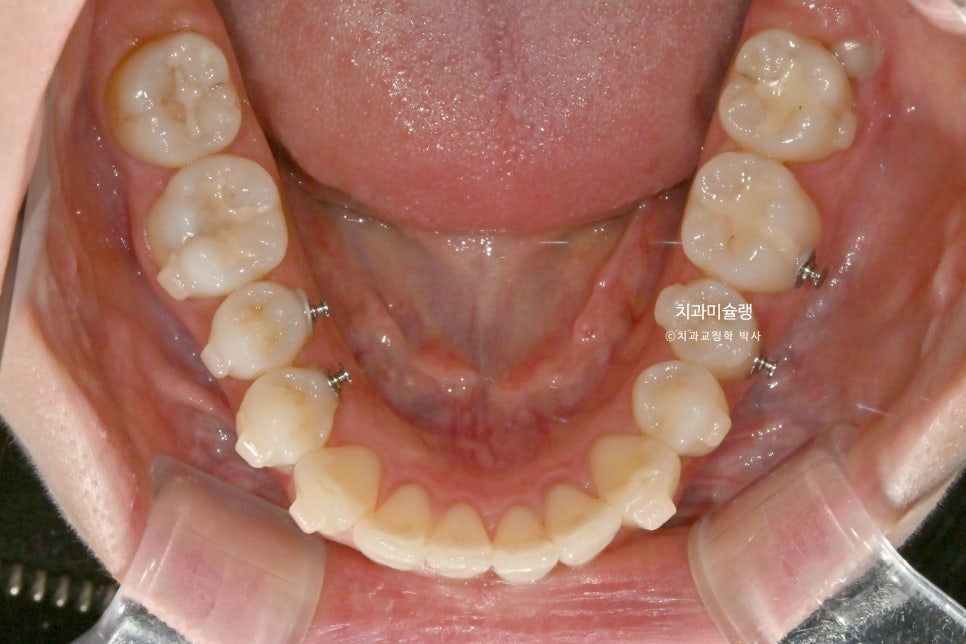

하악소구치 회전의 기술적 어려움

인비절라인 교정에서 투명장치만으로 가장 어려운 치아이동은 바로 <하악소구치의 회전> 입니다.

환자가 아무리 열심히 껴도 어태치먼트 한두개로는 택도 없는

치아이동이기에, 하악 소구치 회전이 요구되는 경우는 부가장치를 붙여서 해결해야 합니다.

여기 저기 붙어있는 금속 고리의 정체는 좀전에 언급한 작은어금니 회전을 위한 부가장치 입니다.

이 부가장치에 고무체인을 걸어놓음으로써 소구치의 회전이 첫세트에서 완료되었는데

4개월간의 회전 개선량을 표시해보면 이러합니다.